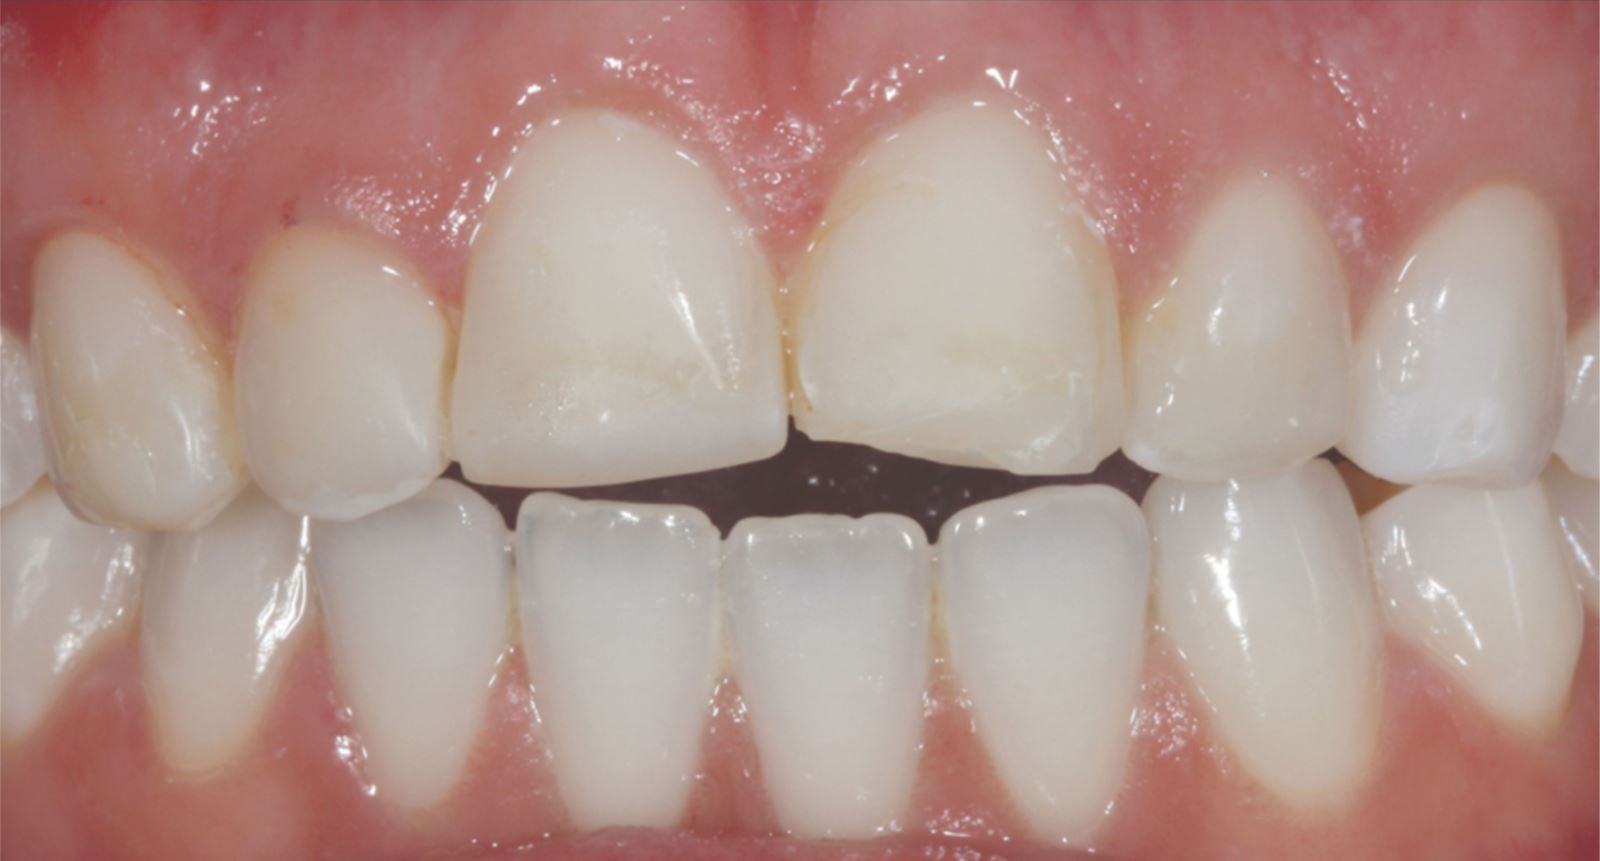

Mladá žena ve věku kolem 20 let, kterou trápila diskolorace horních frontálních zubů po dřívějším traumatu, vyhledala ošetření u Dr. Jaleeny Fischer-Jessop, DDS, MBA. Hledala řešení, které by obnovilo její úsměv. Pacientka byla ošetřena konzervativní a cenově dostupnou metodou: kompozitními fazetami bez preparace, přímým bondingem. Dr. Fischer-Jessop zvolila tento postup k překrytí diskolorace a sjednocení horních zubů s dolními frontálními – bez nutnosti invazivnějších výkonů, jako jsou implantáty, nebo nákladných laboratorně zhotovovaných fazet. Pro zesvětlení zubů byly vybrány odstíny B1D a Enamel White (EW) a odstín Universal Body (UB) kompozitu Transcend™ byl použit k přirozenému splynutí okraje v cervikálních oblastech.

Pacientka měla výrazné estetické obavy a současně byla finančně limitována. S ohledem na tyto okolnosti byly zvoleny kompozitní fazety bez preparace jako vhodné řešení.